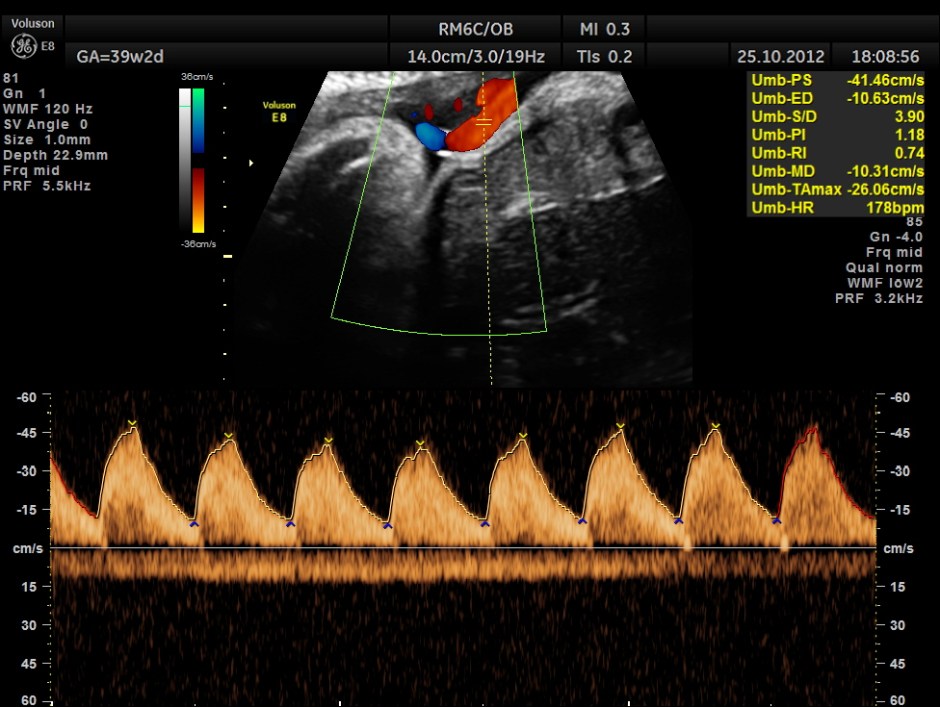

This was a 20 year old lady , primi, has undergone 3 scans earlier at different centres; the last one was done 3 weeks ago and everything appeared normal till then . Now she was referred to rule out cardiac anomaly.

MIDDLE CEREBRAL ARTERY SHOWS HIGH PEAK SYSTOLIC VELOCITY OF 89.1 CMS/S ; M.O.M. WAS AROUND 1.59 SUGGESTIVE OF SEVERE FETAL ANEMIA

THIS FETUS HAD SEVERE FETAL ANEMIA WITH CARDIAC FAILURE LEADING TO CARDIOMEGALY WITH MITRAL, TRICUSPID AND PULMONARY REGURGITATION .NO OTHER OBVIOUS CARDIAC ANOMALY WAS MADE OUT . THE VENO ATRIAL , ATRIO VENTRICULAR AND VENTRICULO ARTERIAL CONCORDANCE APPEARED TO BE NORMAL; NO SEPTAL DEFECT WAS MADE OUT.

ALL THESE HAVE DEVELOPED WITHIN THE LAST 3 WEEKS .